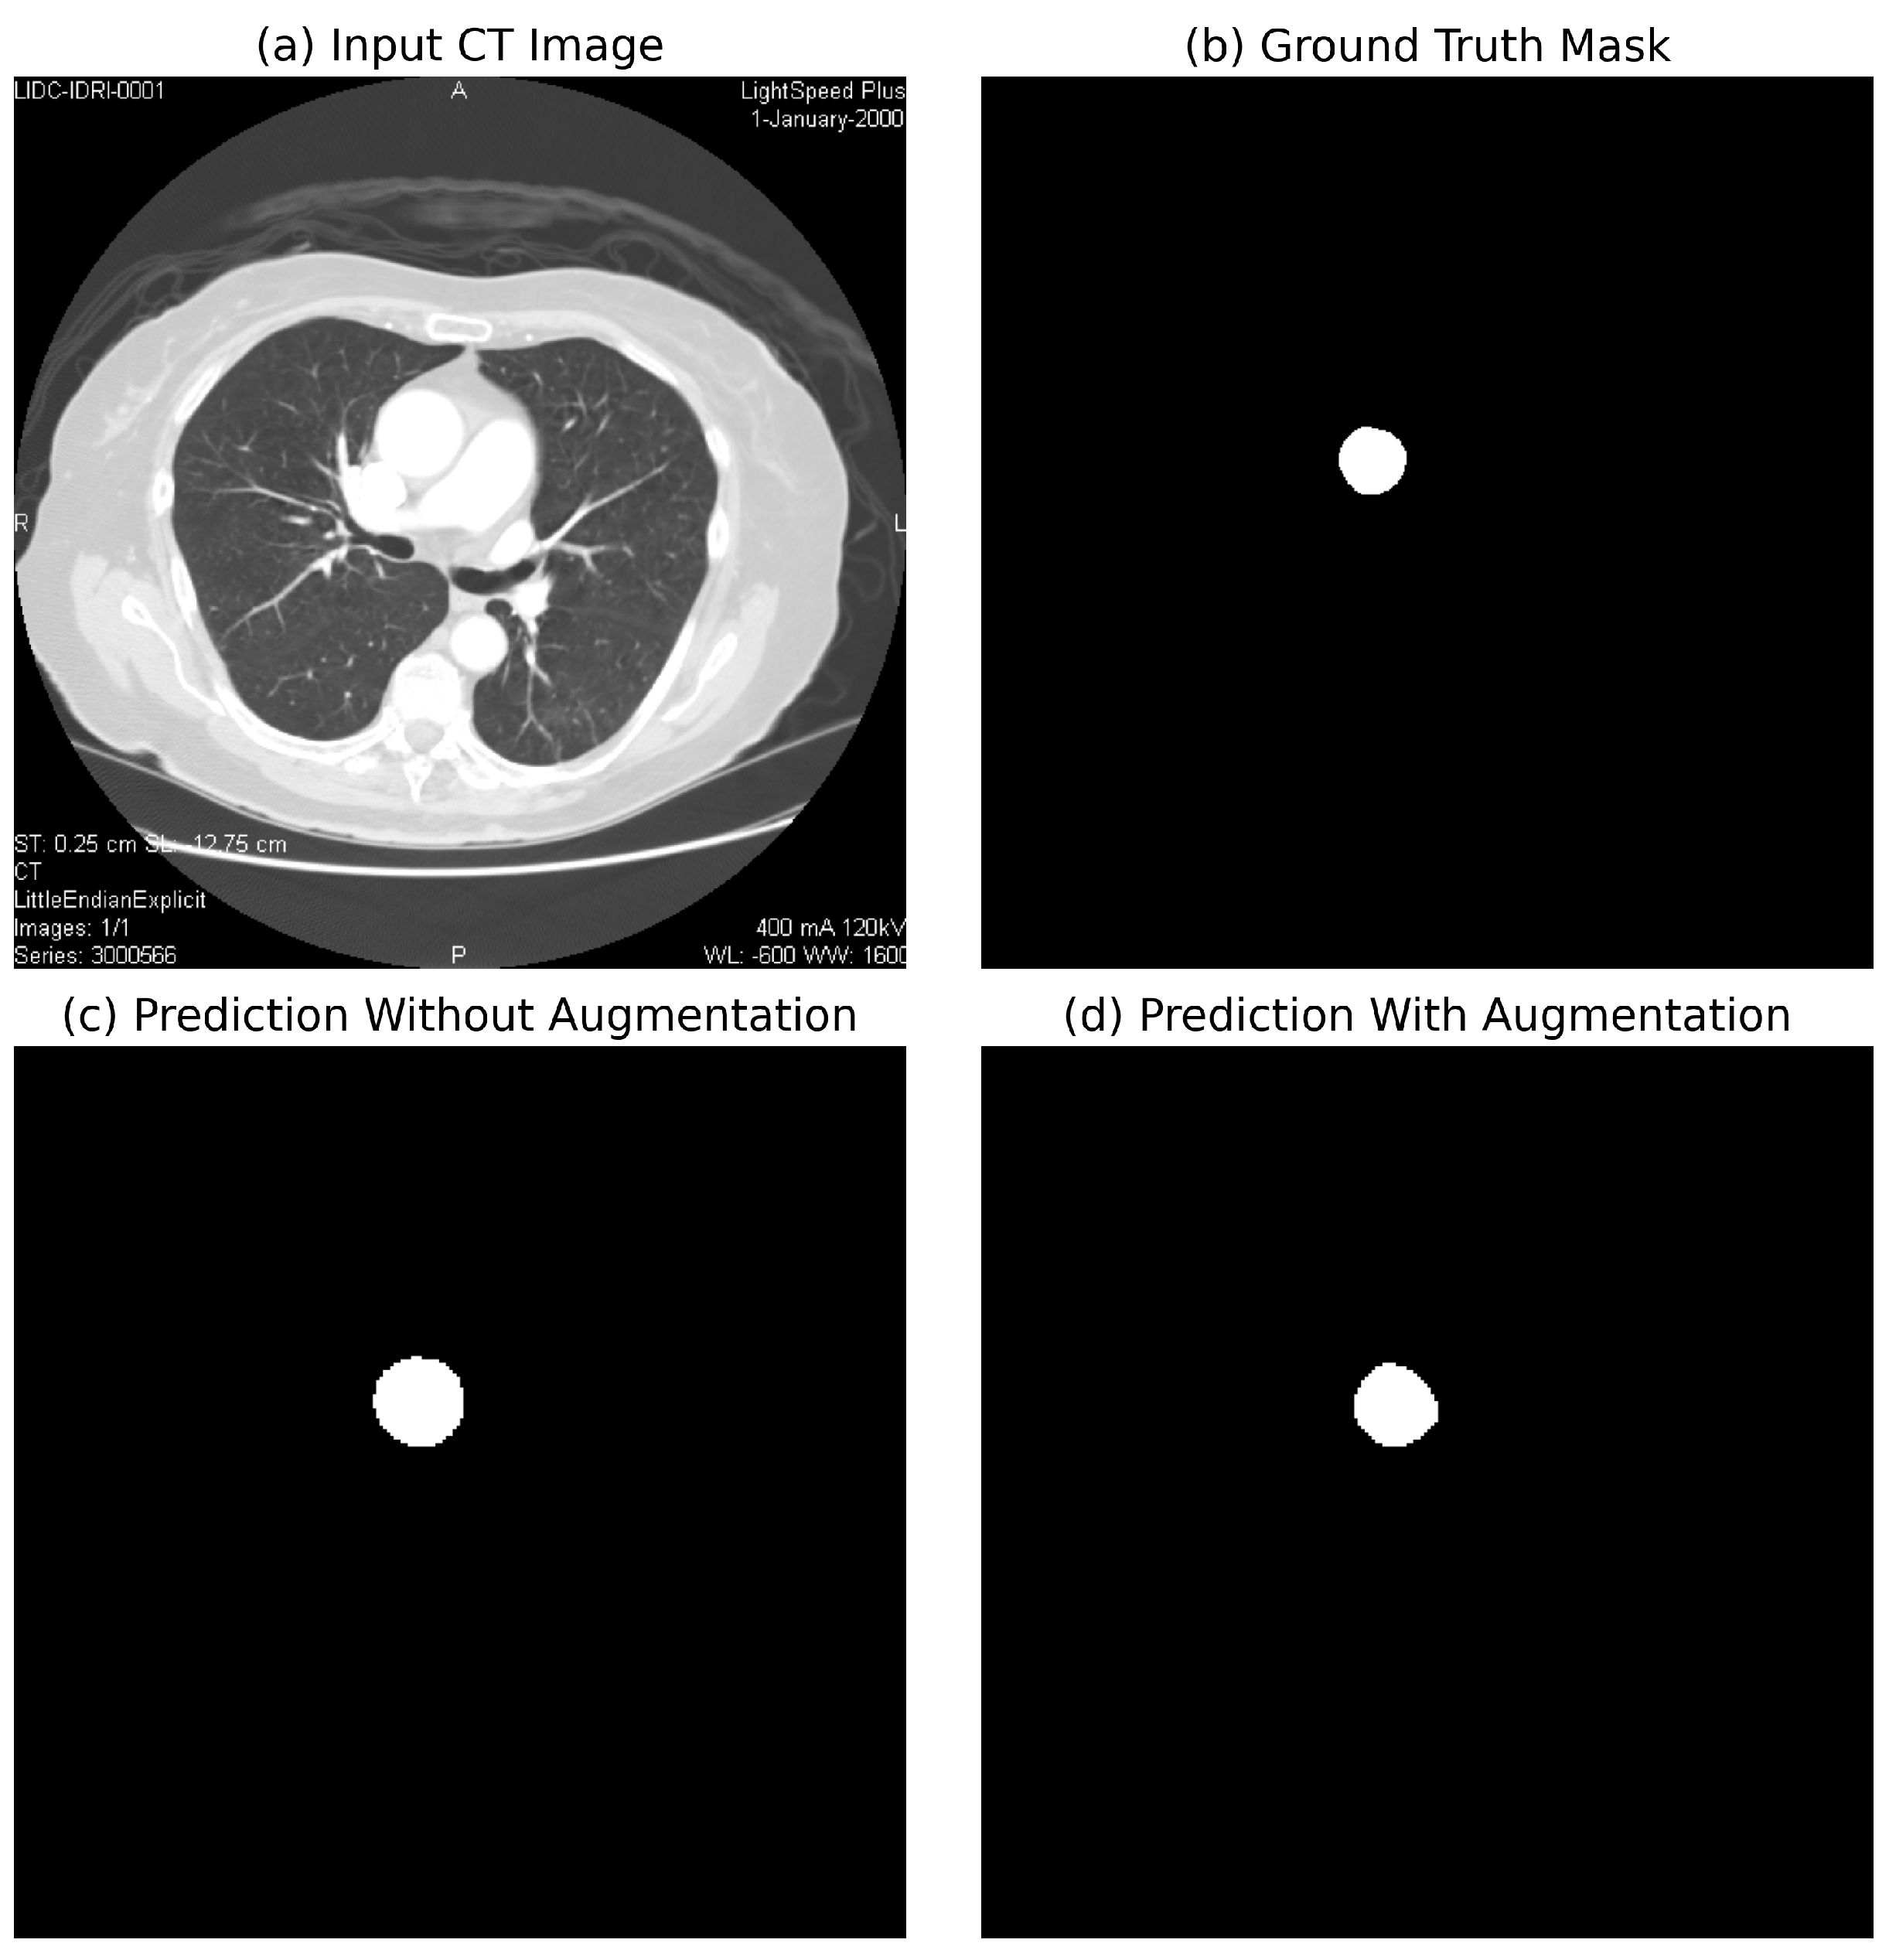

Comparison with Existing Methods: Traditional rule-based segmentation methods report a Dice score of 78.3%, while prior CNN-based methods report Dice scores of 85.6% (basic CNN segmentation) and 90.5% (3D U-Net) [11]. On our held-out test set, the proposed method attains a Dice score of 99.21% and an IoU of 98.45%, representing an 8.7–20.9 percentage-point improvement in the Dice score and a 16.4–33.1 percentage-point improvement in the IoU over reported baselines. An illustrative example of CNN-based focus-slice classification and subsequent U-Net segmentation of the ascending aorta is shown in Figure 1.

Figure 4 compares segmentation performance with and without data augmentation.

Impact of Augmentation: To quantify the effect of augmentation, we compared segmentation performance with and without augmentation. The results indicated a 6.8 percentage-point improvement in the Dice score (86.4% vs. 93.2%) and a 4.3 percentage-point improvement in the IoU (84.2% vs. 88.5%) when augmentation was applied, highlighting its critical role in training deep learning models.

Figure 1. Example of CNN-based focus-slice classification and U-Net segmentation results. The CNN model identifies the most relevant focus slice containing the largest ascending aorta, while the U-Net model accurately segments the aortic region.

Figure 4. Comparison of segmentation performance with and without data augmentation. Augmentation significantly improves model generalization and accuracy.